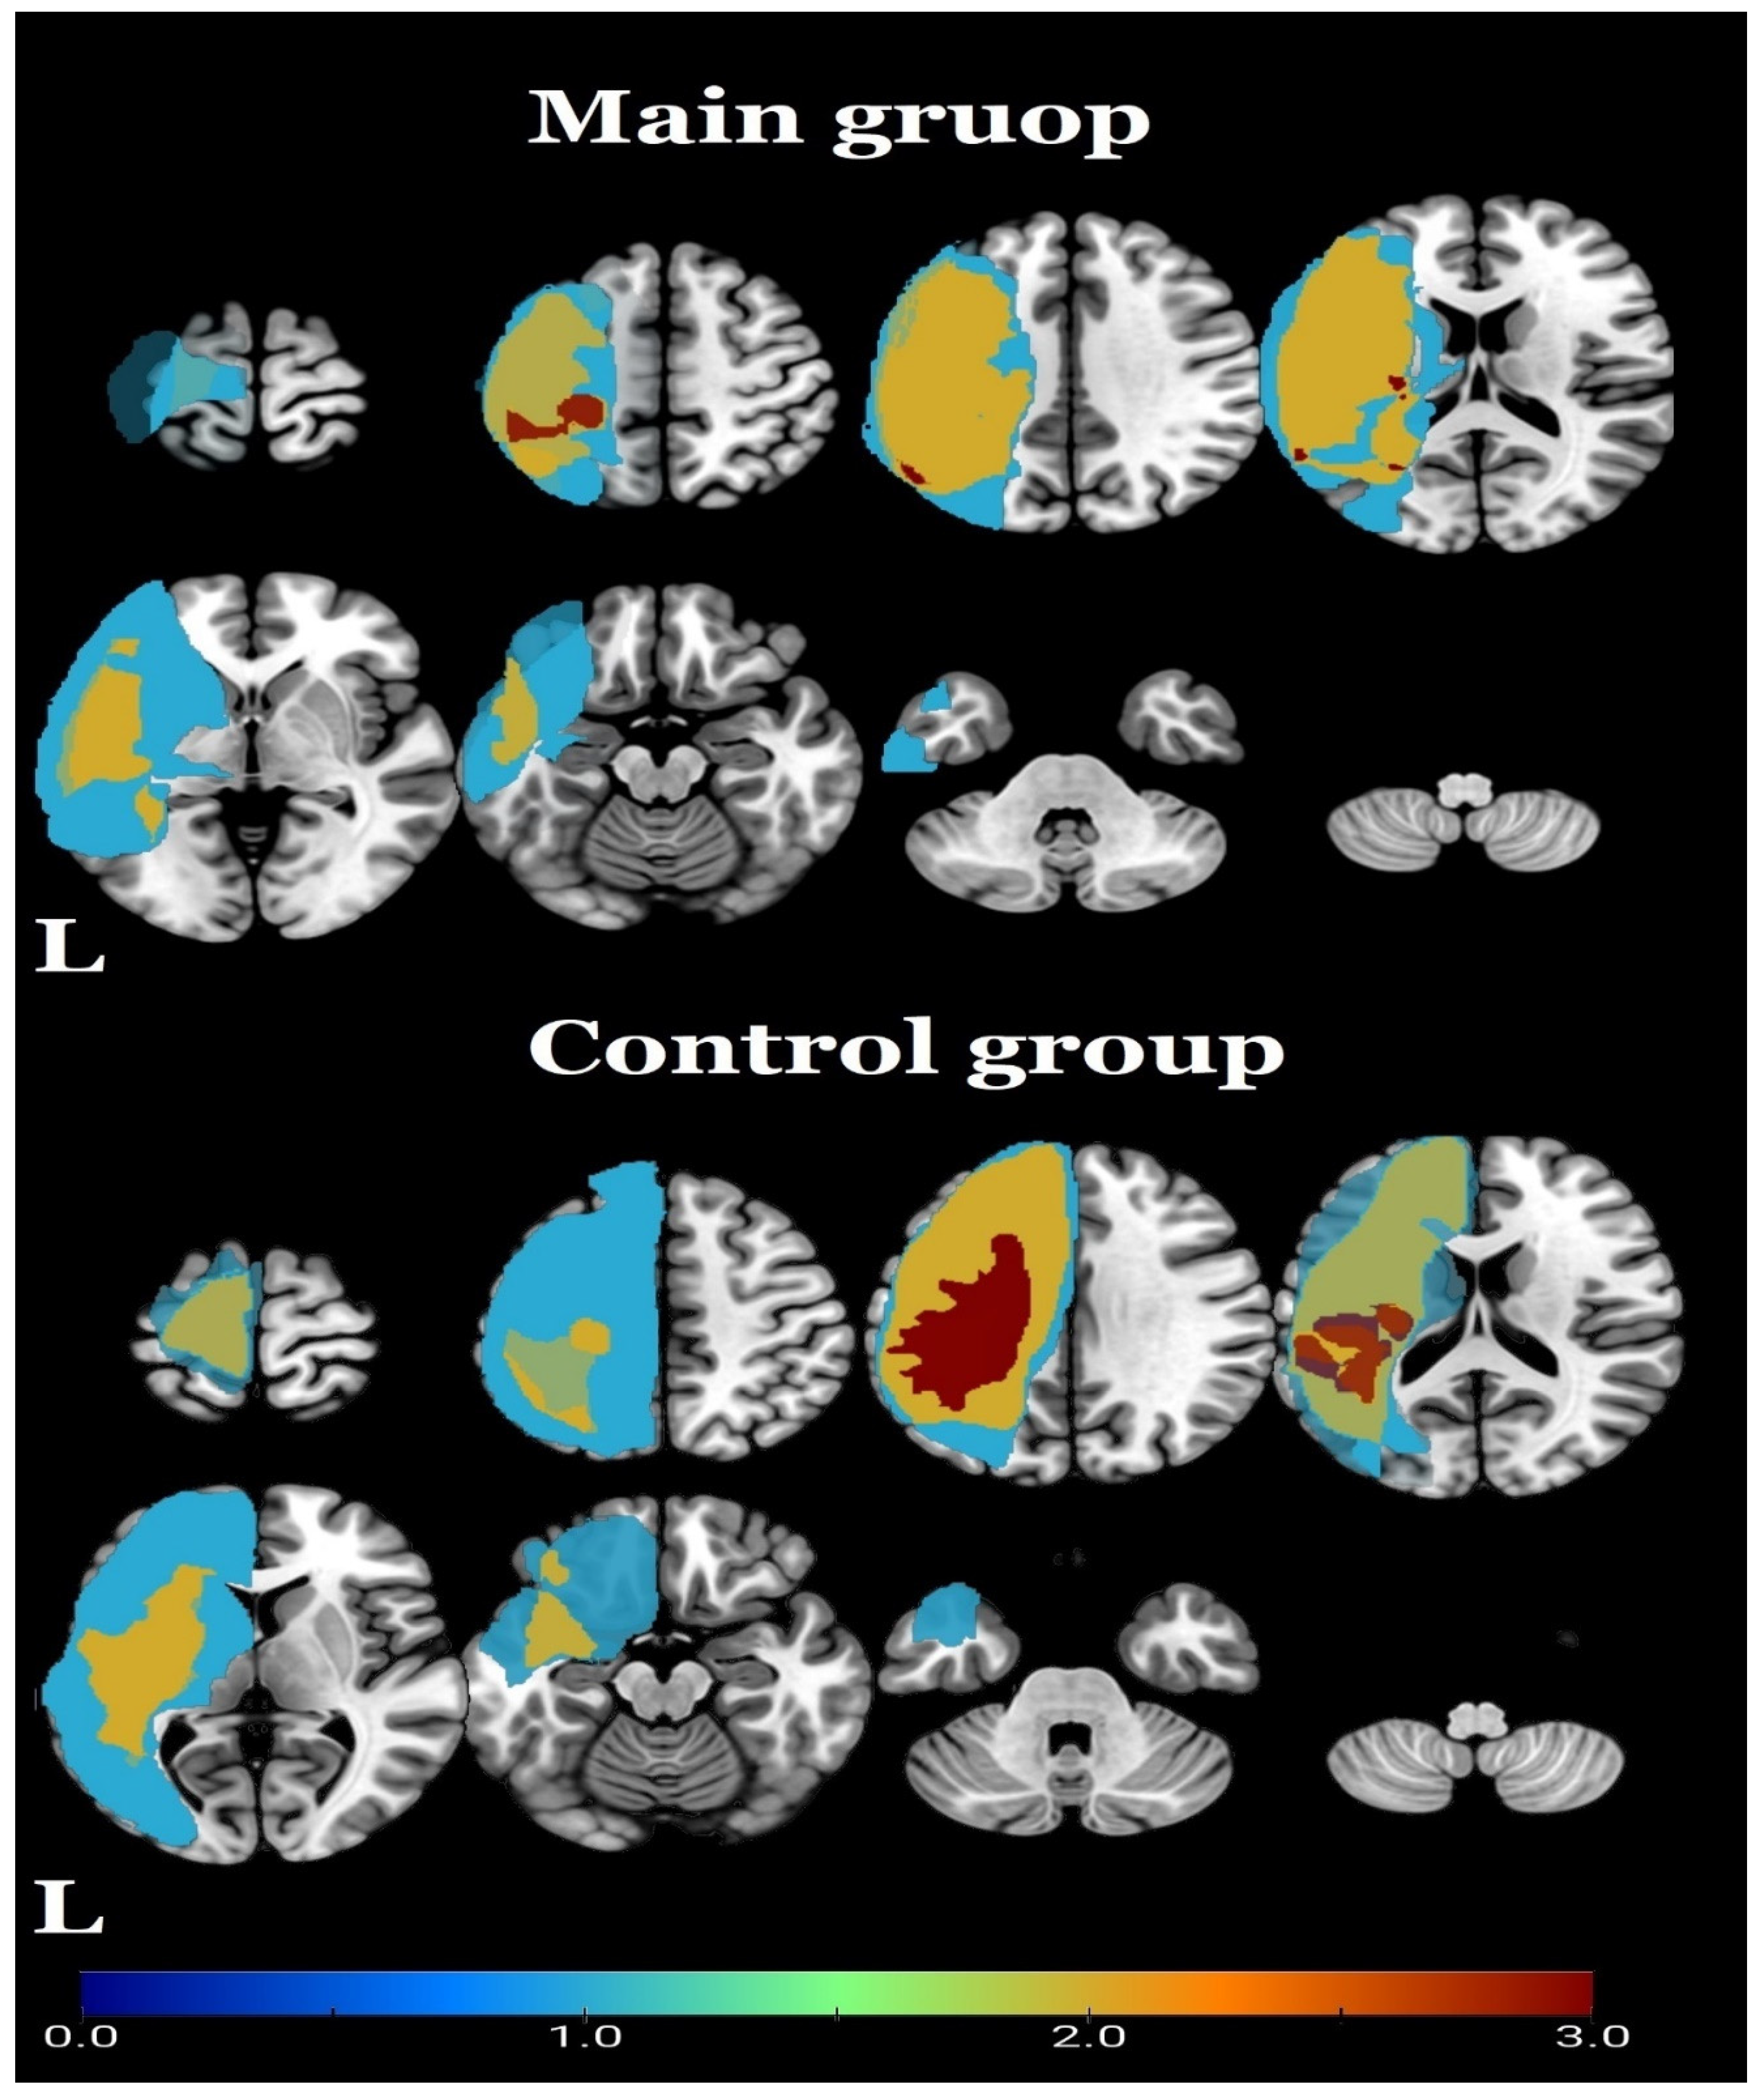

Figure 5.

Seed-to-voxel analysis, t-statistics for changes (2nd control point vs. 1st control point) in functional connectivity in the control group with the seed in the (A) brainstem and (B) right postcentral gyrus (p < 0.05, FDR-corrected); color bars represent negative t-values in blue.

In the control group, there was a decrease in the functional connectivity of the right postcentral gyrus with the central regions of the cerebellum (Figure 5B, Table 4). No significant effects in the right postcentral gyrus as a seed were observed in the main group.

In the present pilot study, it was shown that epidural spinal cord stimulation for a short period resulted in functional changes within the central motor system compared with the controls. The first was higher functional connectivity of the brainstem to the premotor cortex in the right hemisphere, as well as changes in interhemispheric functional connectivity between cortical motor areas; the second was an increase in functional connectivity between the right and left lateral nodes of the sensorimotor network; the third was a positive correlation between the decrease in spasticity and an increase in functional connectivity within the right hemisphere sensorimotor cortex. All these changes in functional connectivity occurred with a statistically significant decrease in spasticity, as assessed by the MAS. Interestingly, in the control group, we did not observe any clinical changes in terms of decreased spasticity during this observation period. Moreover, patients in the control group demonstrated only a decrease in functional connectivity. These reductions were observed in the area of the brainstem with the right temporal pole and the right orbital part of the inferior frontal gyrus, as well as in the right postcentral gyrus with the central regions of the cerebellum.